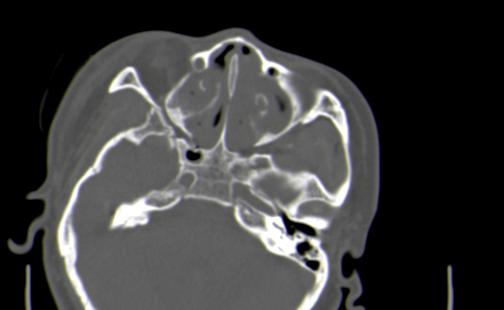

以下是引用皎皎白驹在2006-11-29 8:48:00的发言:[br]影像表现:双侧筛窦和上颌窦、鼻腔内均密度增高,右侧视神经增粗、弯曲,左筛窦顶部筛板及右侧纸板近视神经孔区可见骨折线。[br]结合临床表现考虑:右侧筛窦纸板近视神经孔区骨折致右侧视神经损伤。最好做个眼眶冠状扫描,更明确右侧视神经管是否狭窄。

以下是引用w_jianhua在2006-11-29 10:07:00的发言:[br]影像表现:双侧筛窦和上颌窦、鼻腔内均密度增高,右侧视神经增粗、弯曲,左筛窦顶部筛板及右侧纸板近视神经孔区可见骨折线。[br]结合临床表现考虑:右侧筛窦纸板近视神经孔区骨折致右侧视神经损伤。最好做个眼眶冠状扫描,更明确右侧视神经管是否狭窄。 [br] [br]支持[br]

以下是引用守望可可西里在2006-11-29 9:46:00的发言:[br][quote]以下是引用皎皎白驹在2006-11-29 8:48:00的发言:[br]影像表现:双侧筛窦和上颌窦、鼻腔内均密度增高,右侧视神经增粗、弯曲,左筛窦顶部筛板及右侧纸板近视神经孔区可见骨折线。[br]结合临床表现考虑:右侧筛窦纸板近视神经孔区骨折致右侧视神经损伤。最好做个眼眶冠状扫描,更明确右侧视神经管是否狭窄。